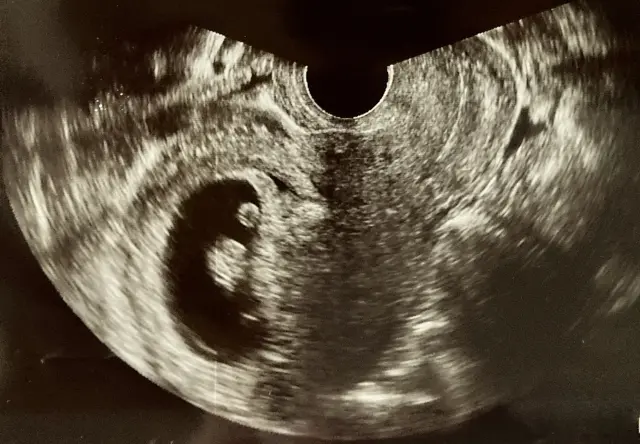

妊娠6週のエコー 胎児の体長は5.7mmです。

妊娠7週のエコー8.7mmまだ大きくなってきています。

妊娠8週のエコー

妊娠9週のエコー